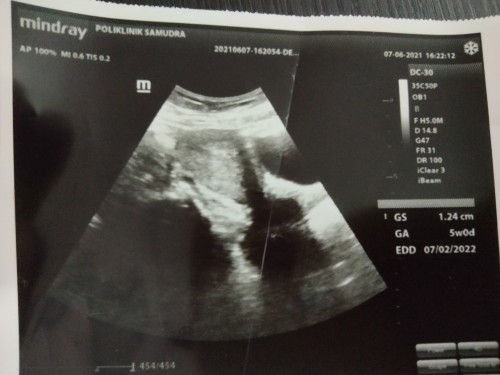

normal sis...saya check up masa 4 minggu apa pun xnampak..dr just cek air kencing..scan just nampak dinding rahim dah tebal means dah pregnant...masa 6 week lebih bleeding...scan kat klinik swasta xnampak jugak baby...just kantung..tpi dr kata mcm kosong...dah sedih...pegi hospital..scan tvs..masuk ikut bawah...alhamdulillah...dpt tgok jantung baby semua...kalau nak tgok baby bawah 9 week melalui tvs boleh..kalau scan biasa mmg xnampak lagi..kalau nampak pun mcm titik hitam je..

5weeks tu ada yg dh bleh nampak,ada yg x nmpak lagi.Mcm sy…5weeks xnmpak lagi.Doc set app utk repeat scan after 2weeks.Alhamdullilah,nampak jantung dia ☺️ Skrg dah masuk 13weeks